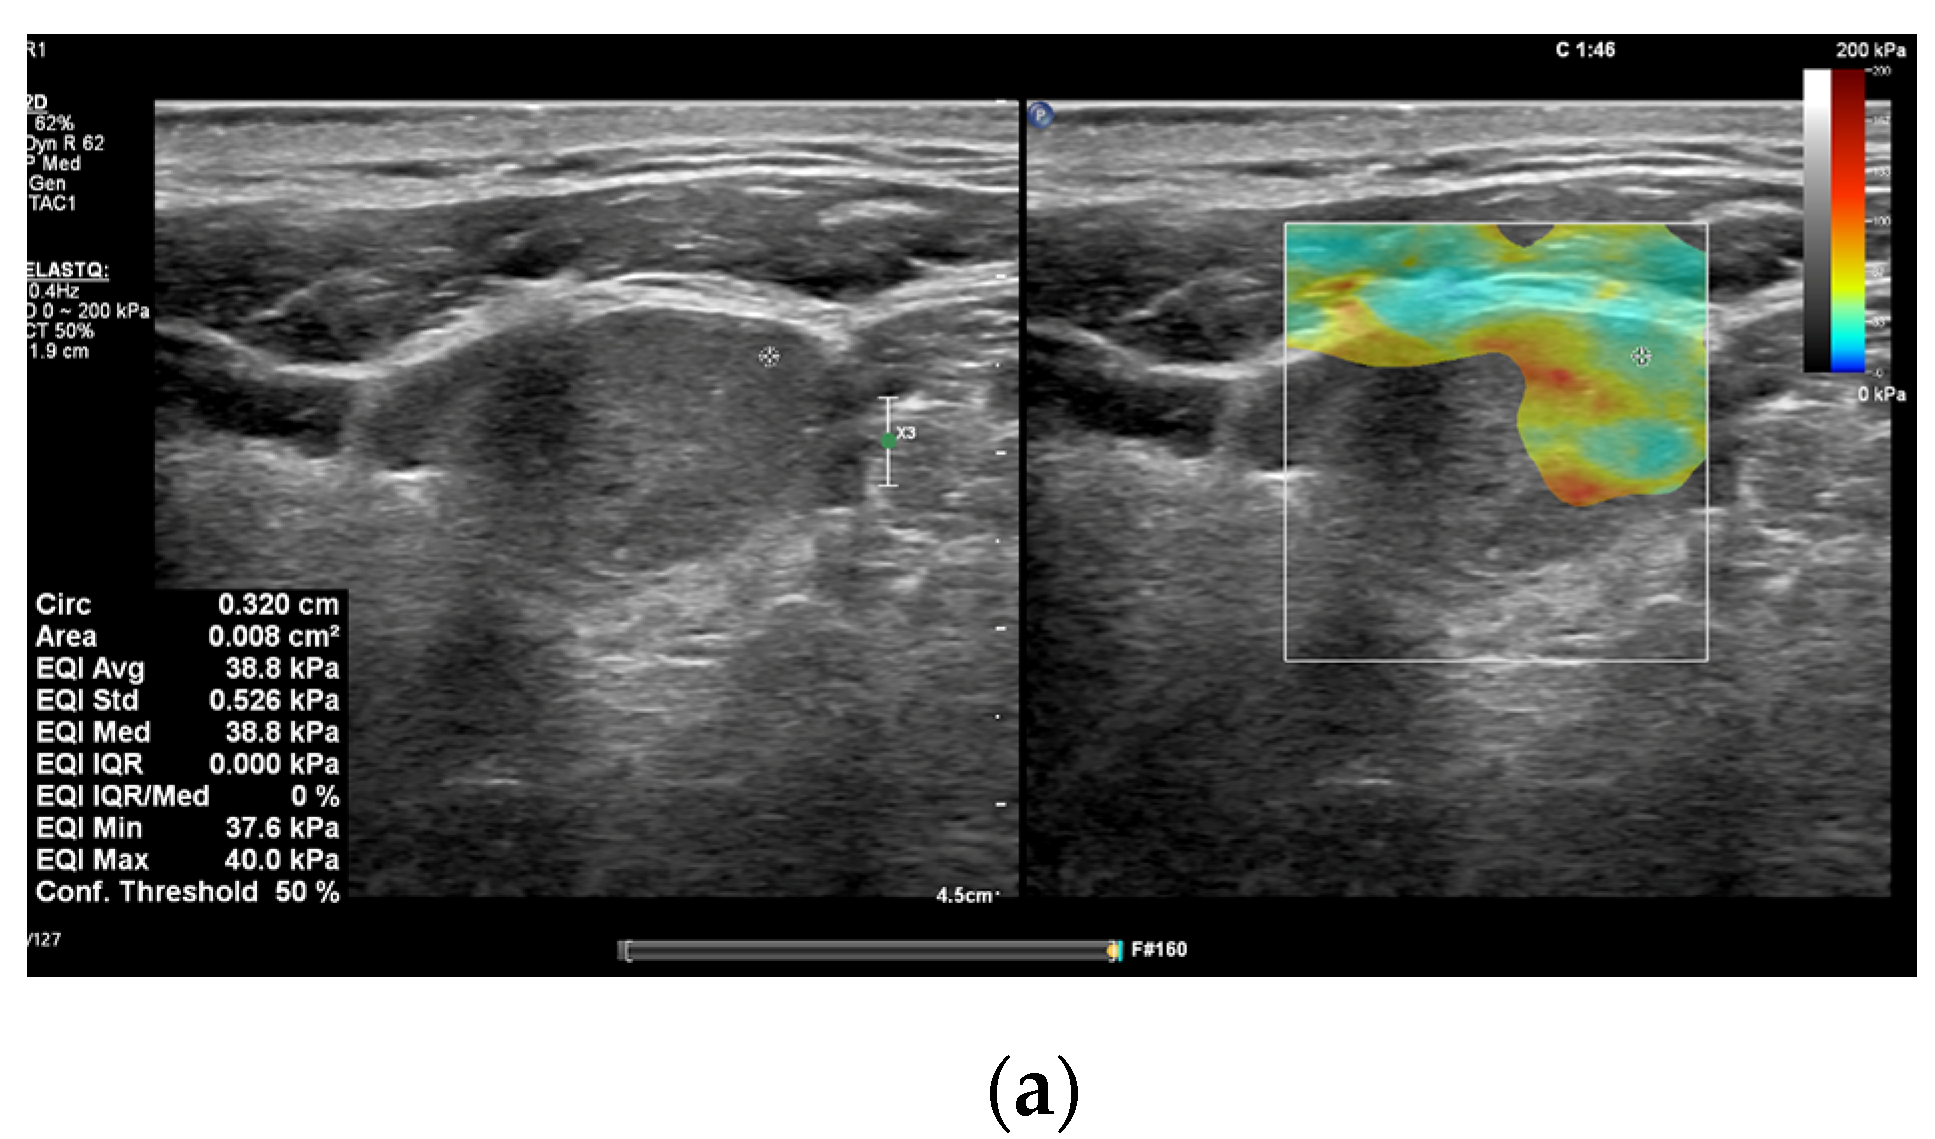

3.1. Elastography

3.2. CEUS